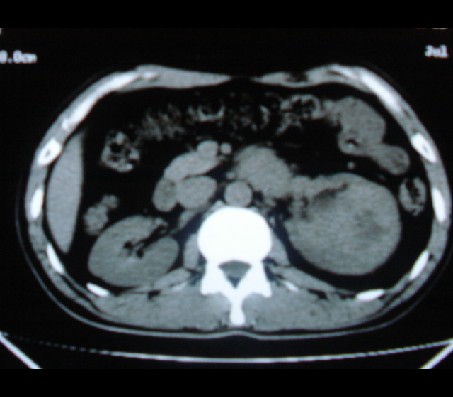

标题: CT20935:左肾占位,请会诊!

男性,35岁,ct号26189,左侧腰痛并血尿一天入院。